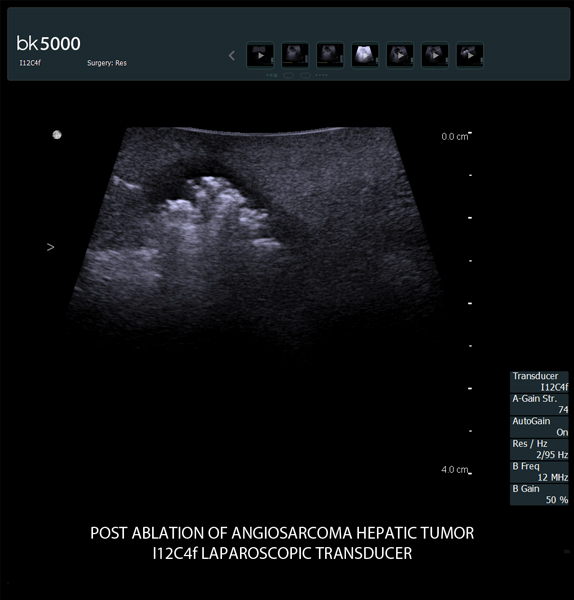

Ultrasound can advance intraoperative surgical procedures by helping you navigate and identify lesions and anatomical structures in real-time. This is particularly important as the data obtained from a preoperative CT or MRI scan can be outdated at the time of surgery.

The bk5000 surgical system provides the highest quality images that allow you to clearly see the margins of a lesion and to determine the best course of action. Using advanced graphics processing technology, this powerful system provides immediate, auto-optimized images that allow you to see the information you need, faster.